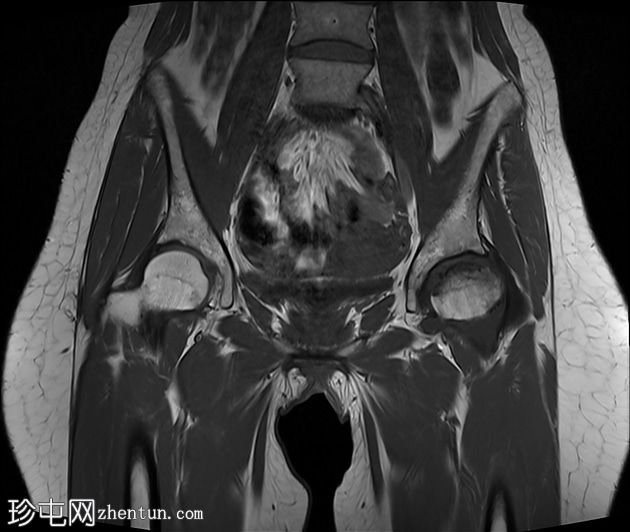

2.jpg

冠状位

T1加权像

左侧股骨头:

T1和T2加权像上可见股骨头前上缘呈蛇形低信号,勾勒出一个地理区域,STIR序列上可见邻近骨髓水肿。

软骨下骨折/新月征,关节面局灶性凹陷——符合软骨下塌陷。

关节间隙中央保持完整,但股骨头轮廓异常,系塌陷所致。

右侧股骨头:

未见骨髓信号异常或软骨下骨折。股骨头轮廓保持完整